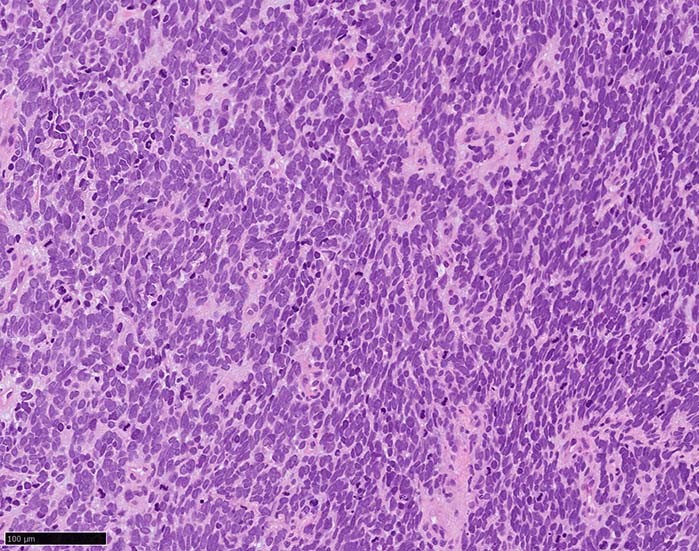

皮膚原発性Merkel細胞癌は 通常真皮を病変首座に増殖し, しばしば脂肪織まで浸潤する.

表皮とは連続性がなくGrenz zoneがみられるのが特徴であるが, 病理所見は多様であり, ときに表皮向性を示す症例やpagetoid patternを呈する症例もある.

典型的な腫瘍細胞は円形, 卵円形の比較的均一な形態で「salt-and-pepper」と称される微細顆粒状クロマチンを有する小型円形核をもつ. MCPyV陽性例が均一な小型円形核を呈する傾向があり, 陰性例では, 核多形性が目立つととする報告がある.

trabecular type, intermediate type, samll cell typeの3パターンの組織型に分類されているがしばしば混在している.

- trabecular typeは円形から多稜形の腫瘍細胞が索状に配列, 3形のなかで腫瘍細胞がもっとも大きく, 円形核と比較的豊富な細胞質をもつ.

- small cell typeは濃いクロマチン, 多形性を示す核をもつN/C比大の小型腫瘍細胞がびまん性に増殖する.

- intermediate typeではtrabecular, samll cell typeの中間の腫瘍細胞サイズを示す. 組織型としてはもっとも多い.

腫瘍内浸潤リンパ球/炎症細胞は多くの症例で認められる. リンパ球の腫瘍内浸潤は予後良好因子と報告されている. 16

血管を間質にしてround cellsが索状に増殖する所見. rossett様配列がある. CK20は特徴的な dot-like patternを示す. クリックで大きな画像が見られます.